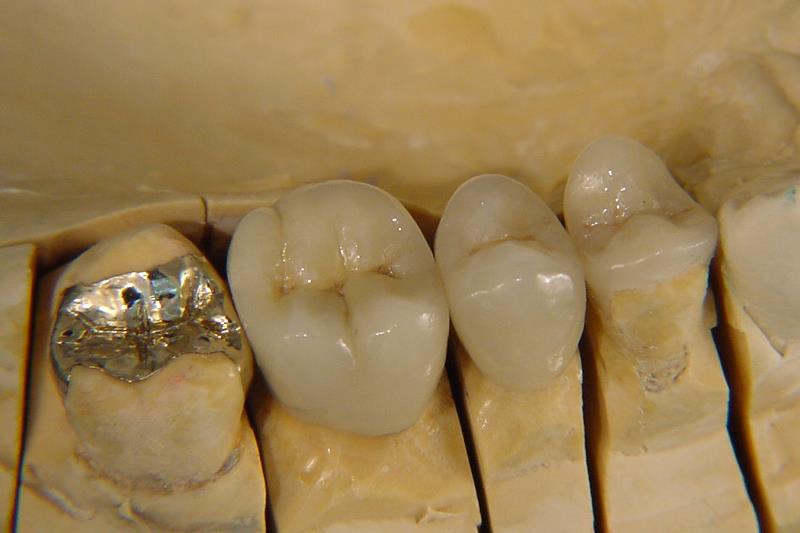

Start » Infos für Patienten » Kronen und Brücken » Teilkronen » Teilkronen in Presskeramik und Gold

Inlay in Gold, Teilkronen in Presskeramik

• Teilkrone auf dem Modell durchleuchtet.

• Presskeramik Teilkrone mit Chamäleon Effekt

• Inlay aus einer Goldlegierung, Teilkrone in Presskeramik

Teilkronen in Presskeramik und Gold

Wenn einZahn nur an der Kaufläche geschädigt ist, kann der Zahn nur zum Teil überkront werden. Es wird mehr natürliche Substanz erhalten. Teilkronen aus Keramik sind eingesetzt fast unsichtbar.